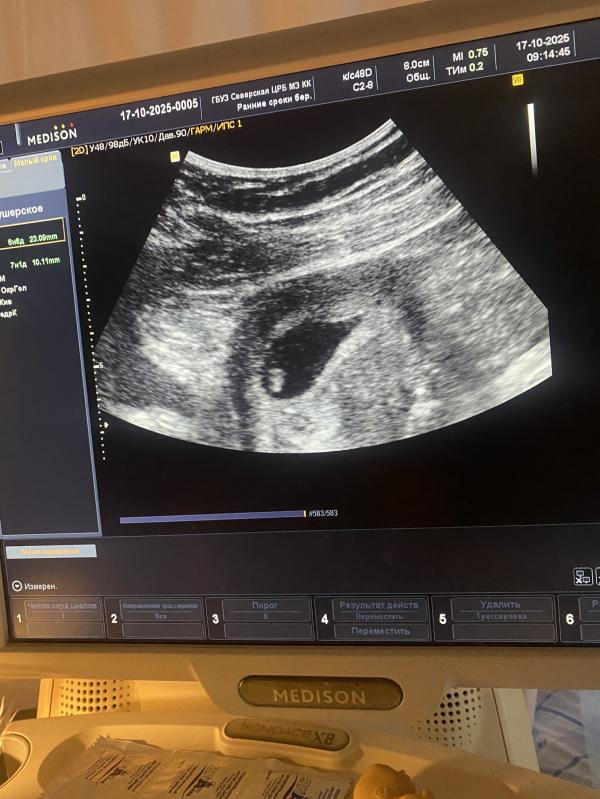

Сходила сегодня на узи, все хорошо ♥️ срок поставили 7 неделек 1день, получается сдвинулись назад на недельку 🙃 сердечко 134удара♥️ вышла и расплакалась 🥹